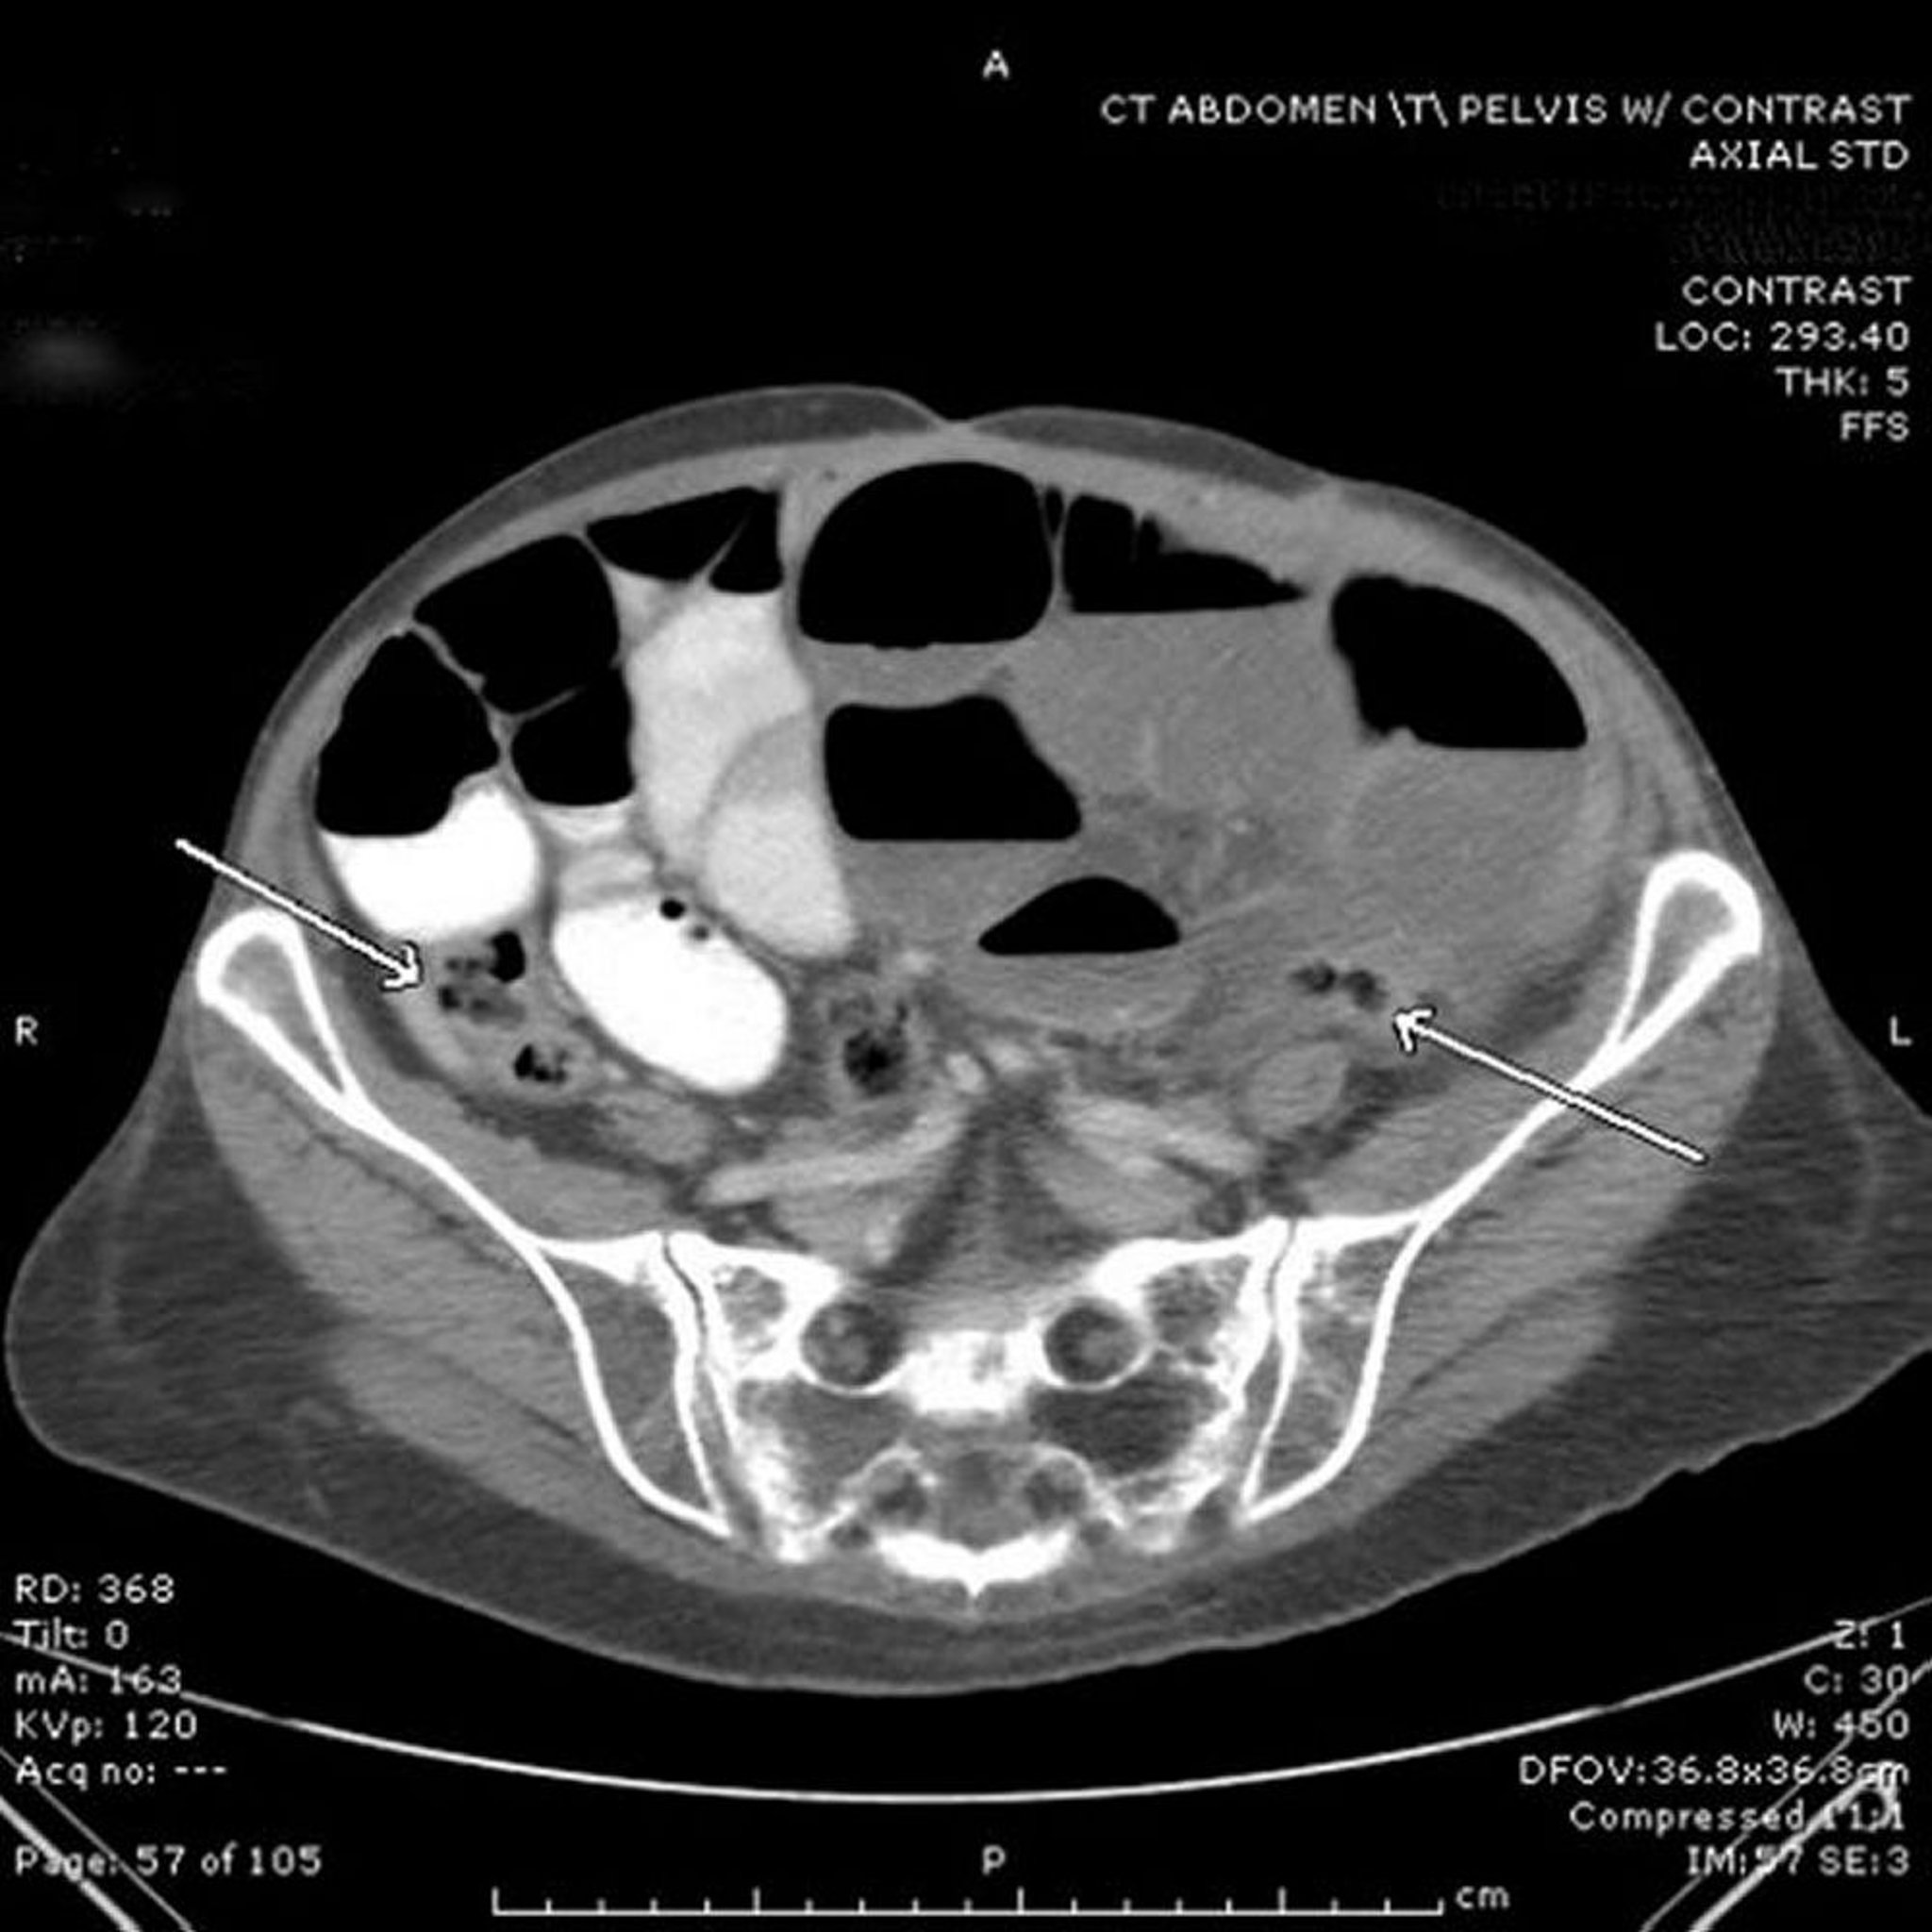

En esta TC, el intestino delgado está dilatado, y lleno de aire y líquido. Se observa contraste oral en algunas de las asas, pero no ha alcanzado el segmento distal del intestino delgado. Obsérvese el ciego y el colon sigmoideo colapsados (flechas). No siempre es posible visualizar un punto específico de obstrucción (punto de transición) en la TC, pero el intestino proximal dilatado y el intestino distal colapsado son altamente sugestivos del diagnóstico.

Image provided by Parswa Ansari, MD.